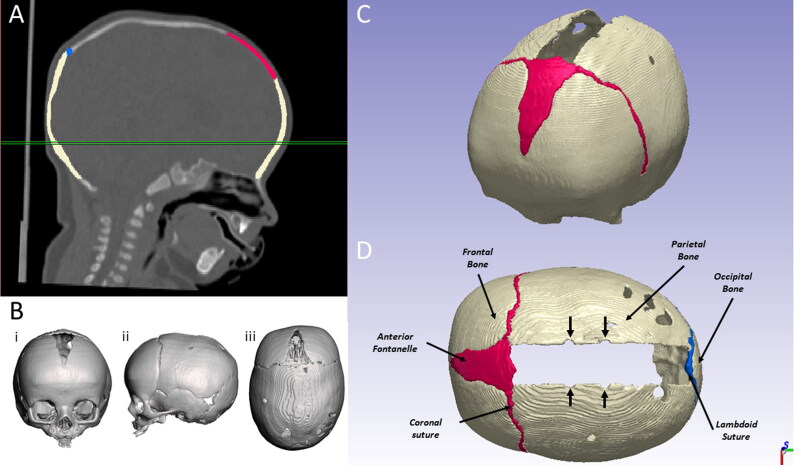

矢状颅畸形(SC)是一种先天性颅面畸形,涉及矢状缝过早骨化;弹簧辅助颅骨成形术(SAC)--插入金属牵引器进行颅骨重塑--是治疗矢状颅畸形的成熟方法。手术结果可通过数值建模预测,但已发表的方法依赖于计算机断层扫描(CT),而这并非常规做法。我们研究了一种基于无辐射三维立体摄影测量扫描的简化方法。八名SAC患者(年龄为5.1±0.4个月)接受了术前CT和三维立体摄影测量扫描。记录了截骨、弹簧模型和术后弹簧张开的信息。为每位患者创建了两个术前模型(PREOP):i) CT 模型;ii) S 模型,该模型通过使用群体平均皮肤和头骨厚度以及缝合位置处理患者特定的三维表面扫描而创建。每个模型都被导入 ANSYS Mechanical(Analysis System Inc.提取相当于术后即刻(POSTOP)和随访(FU)时间的弹簧膨胀率和颅骨指数(CI - 头骨宽度大于长度),并与体内测量结果进行比较。在预测弹簧扩张时,两个模型的结果相当。这项研究表明,根据头部表面形状创建的简化模型在预测弹簧伸缩方面可获得可接受的结果。对模型的进一步改进将有助于在术前规划中使用这一预测工具。

Sagittal Craniosynostosis (SC) is a congenital craniofacial malformation, involving premature sagittal suture ossification; spring-assisted cranioplasty (SAC) - insertion of metallic distractors for skull reshaping - is an established method for treating SC. Surgical outcomes are predictable using numerical modelling, however published methods rely on computed tomography (CT) scans availability, which are not routinely performed. We investigated a simplified method, based on radiation-free 3D stereophotogrammetry scans. Eight SAC patients (age 5.1 ± 0.4 months) with preoperative CT and 3D stereophotogrammetry scans were included. Information on osteotomies, spring model and post-operative spring opening were recorded. For each patient, two preoperative models (PREOP) were created: i) CT model and ii) S model, created by processing patient specific 3D surface scans using population averaged skin and skull thickness and suture locations. Each model was imported into ANSYS Mechanical (Analysis System Inc., Canonsburg, PA) to simulate spring expansion. Spring expansion and cranial index (CI - skull width over length) at times equivalent to immediate postop (POSTOP) and follow up (FU) were extracted and compared with in-vivo measurements. Overall expansion patterns were very similar for the 2 models at both POSTOP and FU. Both models had comparable outcomes when predicting spring expansion. Spring induced CI increase was similar, with a difference of 1.2%±0.8% for POSTOP and 1.6%±0.6% for FU. This work shows that a simplified model created from the head surface shape yields acceptable results in terms of spring expansion prediction. Further modelling refinements will allow the use of this predictive tool during preoperative planning.